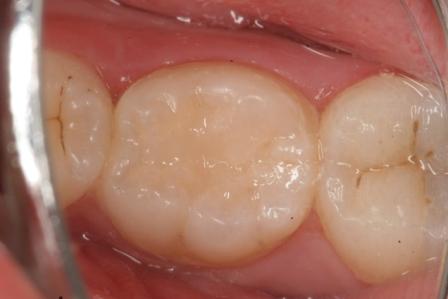

下顎7番の頬側歯茎部カリエスの原因 2025.06.04